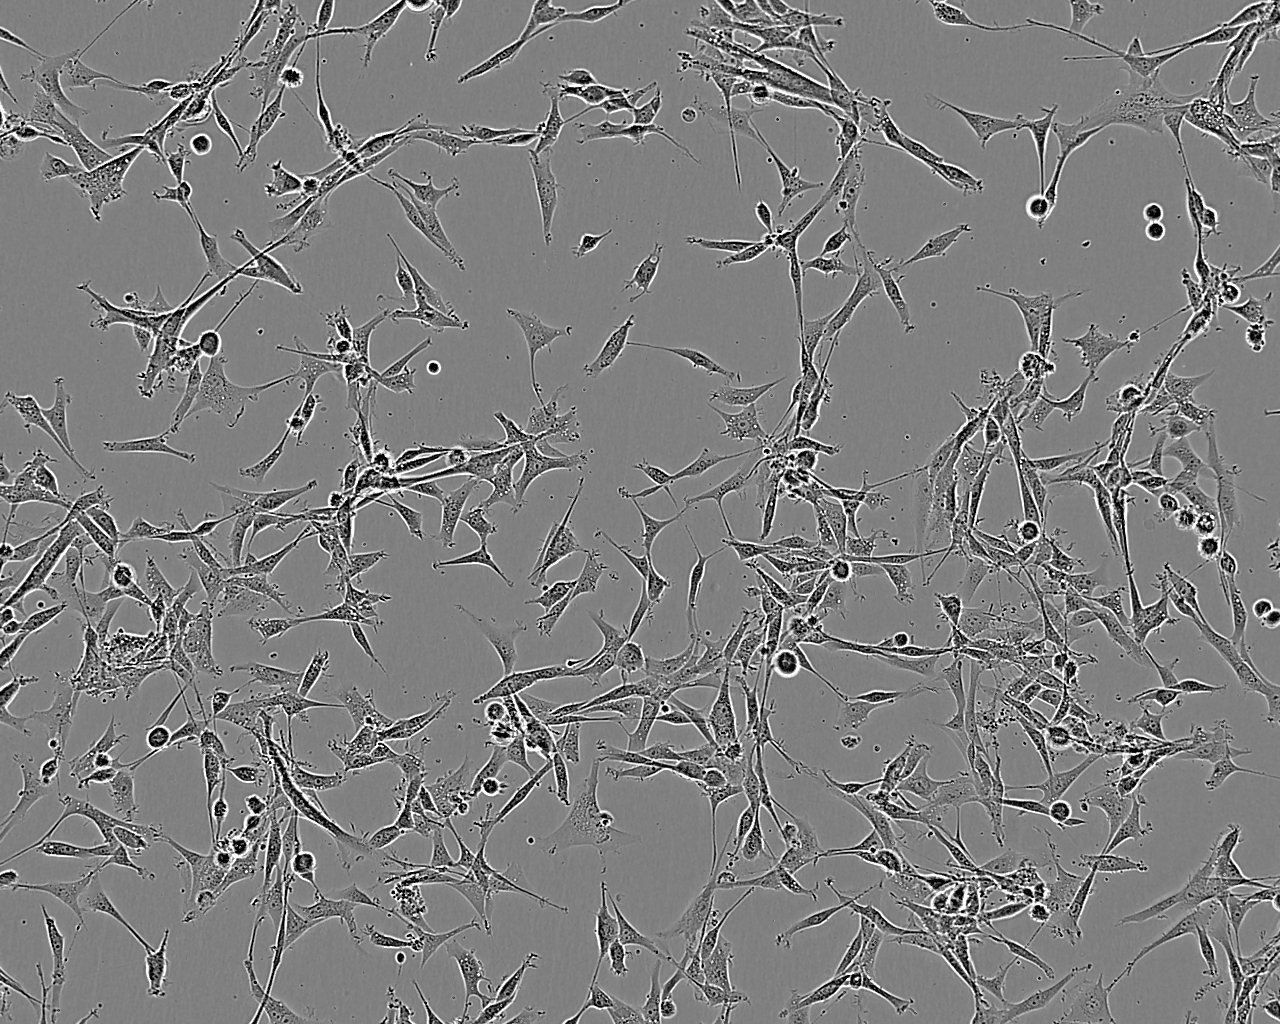

细胞形态:上皮细胞样

细胞生长:贴壁

细胞传代方法:1:2-1:3传代;每周换液2-3次。

细胞生长特性:贴壁或悬浮,详见细胞说明书部分